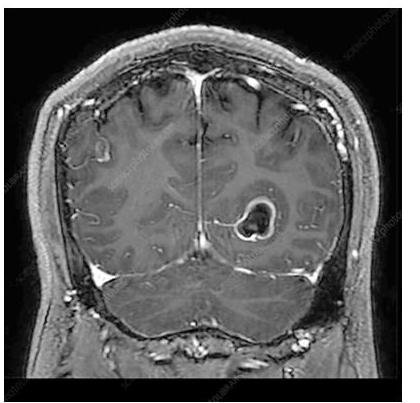

# PARASITOSIS ## DEFINICIÓN **Infecciones intestinales** generadas por **parásitos** en el ser humano, con clínicas variables y poco específicas hasta cuadros **asintomáticos**, sobre todo en adultos; prevalentes en zonas tropicales y con poca higiene debido a contaminación de alimentos o **ingesta directa**. ## EPIDEMIOLOGÍA * La frecuencia en México fluctúa del 2-39 %. * La infección por **Giardia lamblia** es el parásito entérico más frecuente a nivel mundial. * Se calcula que hay 9 millones de infectados por **Giardia lamblia** en México. * También es la más frecuente en ganado, perros y gatos. ## CUADRO COMPARATIVO | | GIARDIASIS | AMEBIASIS | TENIASIS | CISTICERCOSIS | | :--: | :--: | :--: | :--: | :--: | | AGENTE | Giardia lamblia | Entamoeba histolytica | Taenia solium (forma madura) | Quistes larvarios de Taenia solium | | CLÍNICA | Sintomática en niños<br>Diarrea aguda y crónica<br>**Síndrome de Malabsorción**<br>Pérdida de peso | Frecuentemente asintomática<br>Diarrea con moco y sangre (**Disentería**)<br>Puede haber **Abscesos Hepáticos**<br>**Amebomas** (tumores en el ciego) | Dolor abdominal y disminución del apetito.<br>Pérdida de peso.<br>Eliminación de **proglótides** por las heces. | **NEUROCISTICERCOSIS**<br>Cefalea, náusea, vómito.<br>Lesiones ocupantes (**alteraciones visuales**, **ataxia**)<br>Muerte de **quistes** en SNC: **Convulsiones** por respuesta tisular intensa | | DIAGNÓSTICO | 1. **Coproparasitoscópico** en serie de 3<br>2. **Antígeno Fecal** de Giardia en heces.<br>3. Endoscopia o **Entero-Test** | 1. **Examen directo al fresco** de heces.<br>2. **Coproparasitoscópico** | **Coproparasitoscópico** con visualización de **huevos** o **proglótides** | **RM** o **TAC** de cráneo con lesión con **realce en anillo**, **calcificaciones** o **hidrocefalia**. | | TRATAMIENTO | - **Metronidazol** | - **Metronidazol** | - **Praziquantel** | - **Albendazol** (**Neurocisticercosis**)<br>- **Praziquantel** (Cisticercosis sin neuro) | # GIARDIASIS ## DEFINICIÓN Es una enfermedad parasitaria de distribución geográfica cosmopolita, causada por el protozoo **Giardia lamblia**, que frecuentemente ocurre en niños y se caracteriza por el desarrollo de cuadros enterales agudos y crónicos, de intensidad variable y que puede ocasionar un **Síndrome de Malabsorción Intestinal**; en los adultos es comúnmente **asintomática**. ## ETIOLOGÍA Es un protozoo flagelado, mundialmente distribuido, con mecanismos de adaptación que le permiten sobrevivir a condiciones ambientales que de otro modo lo destruirían. Experimenta una variación antigénica a nivel intestinal, lo que le permite un cambio continuo de antígenos de las proteínas de superficie, inhibiendo el reconocimiento por el sistema inmune huésped. **LA FORMA INFECTANTE SON LOS QUISTES** (se adhieren al intestino delgado, produciendo más quistes que posteriormente se excretan).  ## TRANSMISIÓN: * Alimentos y aguas contaminadas (suficiente que contenga **10 quistes** de Giardia). * Animales domésticos como perro o gato. * Ganado vacuno u ovino. * Transmisión sexual oroanal. ## EPIDEMIOLOGÍA * La prevalencia mundial varía desde 1-72 %, dependiendo de la región. * El pico de enfermedad ocurre desde el inicio del verano hasta el inicio del otoño. ## FACTORES DE RIESGO * Población pediátrica (afecta mayormente a preescolares y escolares). * Estancias infantiles. * Viaje a zonas endémicas. * Mala higiene de manos. * Sexo oroanal. * Déficit selectivo de IgA. * Hipogamaglobulinemia. # CLÍNICA Curso **asintomático** desde un 9-57%. ## SÍNTOMAS DIGESTIVOS * **DOLOR ABDOMINAL** (el más común, puede presentarse solo o asociado a otros síntomas). * Considerar sospechoso si tiende a ser recurrente. * Diarrea (aguda o persistente). * Vómito. * Meteorismo. * Distensión abdominal. * Disminución del apetito. * Síndrome de Intestino Irritable. * Fatiga crónica. ## IMPACTO NUTRICIONAL * La Giardiasis afecta la nutrición de los niños debido a un **síndrome de malabsorción intestinal**. * **Retraso del crecimiento** en el 2º año de vida si se adquiere la enfermedad en etapas tempranas. * Disminución sérica de **hierro**, **zinc** y **magnesio**. * **Pobre función cognitiva**. ## OTROS HALLAZGOS Se puede observar en algunos casos lesiones en la retina en forma de degeneración "en sal y pimienta". * Artritis reactiva y sinovitis. * Dermatitis alérgica. * Prurito y urticaria. # DIAGNÓSTICO ## 1ra elección: **Coproparasitoscópicos** en serie de 3. * Se deben identificar los **trofozoítos** o **quistes** en las heces. * Es el examen rutinario de muestras de heces fecales más conocido y usado. * Se realiza en 1er y 2do nivel de atención. ## SI LOS **COPROPARASITOSCÓPICOS** RESULTAN NEGATIVOS Y **PERSISTE SOSPECHA**: ## 2da elección: **Detección de Antígeno Fecal de Giardia lamblia** en heces. Se emplean técnicas de **anticuerpos fluorescentes** y **ensayos inmunoenzimáticos**. ## ESTUDIO ENDOSCÓPICO * Visualización directa con aspirado duodenal y toma de **biopsia**. * No es un estudio de rutina y se reserva para quienes han fallado el **coproparasitoscópico** y los **antígenos fecales**. * Hallazgos en la **endoscopia**: **gastritis antral**, **duodenitis**, **úlcera duodenal**. * **Histopatológico**: infiltración de **lámina propia** por granulocitos, linfocitos y células plasmáticas, **hiperplasia linfoide nodular** y **atrofia de vellosidades intestinales**. ## ENTERO-TEST * Se requiere que el paciente trague la cápsula y la cuerda. * Posteriormente se visualiza con microscopio y tinción directa posterior a obtener la cuerda. * Requiere personal experimentado y se realiza solo en el 2do nivel. ## PCR * Es un estudio muy **sensible** y **específico** y permite identificar la **morfología** del parásito. * Pocos laboratorios cuentan con este estudio y solo se realiza con fines de investigación en el 3er nivel. # TRATAMIENTO Debido a que los pacientes **asintomáticos** con infección por Giardia lamblia expulsan los quistes y se convierten en fuente de infección para su comunidad y entorno, se debe **INICIAR TRATAMIENTO EN TODOS LOS CASOS**. ## 1ra elección: **Metronidazol** * Tiene una eficacia de 60-100% en adultos y niños. * Dosis: 5 mg/kg/dosis 3 veces al día por 5 días. * Debe suspenderse si presenta intolerancia al medicamento. * Evitar alcohol por reacción **Disulfiram**: Inhibición de la oxidación del alcohol por bloqueo de la enzima aldehído deshidrogenasa, provocando una elevación de niveles de acetaldehído. ## 2da elección: **Tinidazol en monodosis** * En caso de que el Metronidazol no sea bien tolerado. * Indicado en niños de poblaciones de bajos recursos. ## ALTERNATIVAS: * **Metronidazol** + **Albendazol** (en caso de resistencia). * **Paromomicina** (indicada en 1er trimestre de embarazo). * **Secnidazol**. * **Albendazol**. * **Furazolidona**. * **Nitazoxanida**. ## PERSISTENCIA DE LOS SÍNTOMAS * Resistencia farmacológica. * Cura seguida de **reinfección**. * Falta de apego al tratamiento. * Intolerancia a la **lactosa post-giardiasis**. * Inmunodeficiencias. ## EVALUACIÓN POSTERIOR Vigilar de manera rutinaria con nuevas muestras fecales a los 3-5 días de finalizar el tratamiento. ## REFERENCIA Envío a 2do nivel: * Síntomas sugestivos de Giardia lamblia + **Coproparasitoscópico** seriados negativos. Envío a 3er nivel: * Síntomas + **Coproparasitoscópico** Negativos + **Antígeno fecal** negativo. # AMEBIASIS ## DEFINICIÓN Es una infección intestinal parasitaria, de distribución mundial y provocada por la **Entamoeba histolytica** que tiene como hábitat el intestino grueso. Su característica es que puede presentar **diseminación hematógena**, provocando un **absceso hepático**, así como **amebomas** en el colon. ## ETIOLOGÍA La **Entamoeba** presenta dos formas: **TROFOZOÍTO**: forma vegetativa invasora, plasma hialino, puede contener glóbulos rojos. **QUISTE**: Forma resistente a los antibióticos. Esférico de 10-15 micras (**ELEMENTO INFECTANTE**). ## Transmisión: * Agua y alimentos contaminados. * Fecal/Oral. * Contacto directo. * Fómites. * Transmisores biológicos. ## EPIDEMIOLOGÍA * Es más frecuente en áreas tropicales o subtrópicas. * La presentación **EXTRAINTESTINAL** más frecuente se sitúa en el **HÍGADO** (formando **absceso hepático**). ## FACTORES DE RIESGO * Contaminación fecal de agua y alimentos. * Mala higiene de manos. # FACTORES PARA FORMACIÓN DE ABSCESO: * Sexo masculino. * 3ra a 5ta década de la vida. * Alcoholismo. * Padecimientos oncológicos. * Prácticas homosexuales. * Inmunosupresión. * Habitar o viajar a zonas endémicas. * Uso de corticosteroides. ## CLÍNICA ## ASINTOMÁTICO Es la presentación más **frecuente**. ## DIARREA * Con **disentería grave** (moco y sangre). * Puede haber **ulceración colónica**. ## ABSCESO HEPÁTICO * Fiebre vespertina o nocturna no muy alta. * Dolor en hipocondrio derecho. * Hepatomegalia. * Ictericia. * Escalofríos y malestar general. ## AMEBOMAS * Masas pseudotumorales en el ciego. ## DIAGNÓSTICO 1. **EXAMEN DIRECTO AL FRESCO DE HECES** (serie de 3) o secreciones. a. Búsqueda de **trofozoítos**. b. Es el estudio diagnóstico definitivo. 2. **COPROPARASITOLÓGICO** de concentración, para amebiasis crónica. a. Búsqueda de **quistes** (3 series). 3. **BIOPSIAS DE ÚLCERAS** (**trofozoítos**). a. Se realiza con tinción de **hematoxilina**. # TRATAMIENTO ## 1ra elección: **Metronidazol**, **Tinidazol** o **Cloroquina** * Son **amebicidas tisulares**. ## 2da elección: **Paromomicina**, **Ioquinol**, **Furoato de Diloxanida** * Son **amebicidas luminales**. ## PORTADORES ASINTOMÁTICOS En caso de detectarse familiares de infectados pero **asintomáticos**, se iniciará un **fármaco luminal**. 1ra elección: **Yodoquinol** por 20 días. ## ABSCESO HEPÁTICO AMEBIANO 1ra elección: **Metronidazol** + **amebicida intraluminal** (**Furoato de Diloxanida**, **Paromomicina**). ## 2da elección: * Si hay intolerancia a **Metronidazol** o **Tinidazol**. * Si hay intolerancia a **imidazoles** o **Nitazoxanida**. ## PUNCIÓN PERCUTÁNEA * Persistencia de síntomas clínicos de 72 horas de iniciado el tratamiento. * Datos de ruptura inminente. * Absceso de lóbulo hepático izquierdo. * Embarazo y contraindicación del uso de Metronidazol. * Complicaciones pleuropulmonares. ## ABORDAJE LAPAROSCÓPICO * Drenaje por esta vía si hay fracaso en el percutáneo. ## ABORDAJE LAPAROTOMÍA * En caso de ruptura del absceso a cavidad peritoneal. ## FACTORES DE MAL PRONÓSTICO ABSCESO HEPÁTICO * Abscesos múltiples. * Volumen >500 ml. * Elevación del hemidiafragma derecho (o derrame pleural). * Bilirrubina >3.5 mg/dL. * Hemoglobina <8 mg/dL. * Albúmina <2 g/dL. * Diabetes mellitus. # TENIASIS ## DEFINICIÓN La infección por **Taenia solium** es una infección intestinal por **TENIAS ADULTAS**, que se produce tras la **ingestión** de **carne de cerdo contaminada** o de carne ovina en el caso de **Taenia saginata**, madurando en el intestino. ## ETIOLOGÍA El ser humano es el **huésped definitivo**. * Taenia solium. * Taenia saginata. 1. Los seres humanos ingieren **carne de cerdo con cisticercos** (**larvas**) cruda o poco cocinada. 2. Después de la ingestión, los **quistes** se evaginan, se adhieren al intestino delgado por sus **escólices** y maduran para convertirse en **tenias adultas** en unos 2 meses. 3. Las **tenias adultas** producen **proglótides**. Las **proglótides grávidas** se desprenden de la tenia y migran hacia el ano. 4. Tras desprenderse, las **proglótides** o los **huevos** salen del **huésped definitivo** (humano) a través de las heces. 5. Los cerdos o los seres humanos se infectan al ingerir **huevos embrionados** o **proglótides grávidas** (p. ej., en alimentos contaminados con materia fecal). La **autoinfección** puede producirse en los seres humanos si las `proglótides` pasan del intestino al estómago por movimientos antiperistálticos.  6. Una vez ingeridos los **huevos**, se incuban en el intestino y liberan **oncosferas**, que penetran en la **pared intestinal**. 7. Las **oncosferas** se desplazan por el **torrente sanguíneo** hasta los **músculos estriados**, el **encéfalo**, el **hígado** y otros órganos, donde se convierten en **cisticercos**. En estos pacientes, puede producirse la **cisticercosis**. **PROGLÓTIDE**: es lo que se encuentra en las heces y por lo general es el motivo de consulta al observarlo en las evacuaciones. La **taenia** suele alcanzar los 4 metros de longitud (se suman los `proglótides` y el `escólex`). # EPIDEMIOLOGÍA Las **tenias adultas** pueden residir en el intestino delgado durante varios años; pueden alcanzar los 2 a 7 m de longitud y producir hasta 1.000 **proglótides**, cada una con alrededor de **50.000 huevos**. El ser humano es el **huésped definitivo**.  ## FACTORES DE RIESGO * Carne mal cocida. * Viaje a zonas endémicas. * Contaminación fecal de agua y alimentos. ## CLÍNICA * Excreción **asintomática** de **proglótides**. * **Náusea**, **anorexia**, **dolor epigástrico**. ## DIAGNÓSTICO  ## **Coproparasitoscópico** **Visualización** de **huevos** o **proglótides**. * La infección por **gusanos adultos** de *T. solium* suele poder diagnosticarse mediante el **examen microscópico** de muestras de heces y la identificación de **huevos**, **proglótides** o ambos. * Los huevos de *T. solium* se encuentran en \leq 50% de las muestras de heces de pacientes con **cisticercosis**. * Los huevos son indistinguibles de los de *T. saginata* y *T. asiatica*. ## TRATAMIENTO ## 1ra elección: **Praziquantel** * Una sola dosis de 5 a 10 mg/kg de **prazicuantel** por vía oral para eliminar los **helmintos adultos**. * Provoca alteración en el flujo de iones de calcio de las células del parásito, generando una contracción muscular y paralizándolo. * Precaución en pacientes que también tienen **neurocisticercosis**, porque al matar los **quistes**, el **prazicuantel** puede desencadenar una **respuesta inflamatoria** asociada con **convulsiones** u otros síntomas. # CISTICERCOSIS ## DEFINICIÓN La **cisticercosis** es una infección parasitaria de los tejidos causada por los **QUISTES larvarios** de la tenia porcina. Estos **quistes** infectan el **cerebro**, los músculos y otros tejidos y son una de las causas principales de **epilepsia** en los adultos de la mayoría de los países de bajos ingresos. Una persona puede contraer cisticercosis al **ingerir los huevos** excretados por alguien que tiene **tenia intestinal**. ## ETIOLOGÍA Los **cisticercos** son una forma intermedia en el desarrollo del parásito (entre el embrión y el hexacanto). Los que producen **neurocisticercosis** son las especies de *Taenia solium*. En la mayoría de los órganos, los **cisticercos viables** (**larvas**) causan una **reacción tisular mínima** o nula, pero la muerte de los **quistes** en el **SNC** puede desencadenar una **respuesta tisular intensa**. En consecuencia, los síntomas suelen no evidenciarse hasta varios años después del contagio. ## EPIDEMIOLOGÍA * La **cisticercosis** no se contrae por comer carne de cerdo mal cocida (**Teniasis**) sino por la **ingesta** de **larvas** (**huevos** o formas inmaduras de la **Taenia**) excretadas en las heces humanas. * Las personas que viven en el mismo hogar del portador de la tenia tienen un riesgo más alto de contraer cisticercosis que otras personas. ## FACTORES DE RIESGO * Zonas de América Latina, Asia y África donde haya malas condiciones de saneamiento. * Cría de cerdos sueltos que pueden estar en contacto con heces humanas. ## CLÍNICA El **cisticerco** puede afectar al músculo y al **sistema nervioso central**. ## NEUROCISTICERCOSIS * **Lesiones quísticas** que evolucionan a **calcificaciones**. * **Cefalea**. * **Náusea** y **vómito**. * **Alteraciones visuales**. * Inestabilidad. * **Ataxia**. ## **Convulsiones**: Relacionadas con la **inflamación** que rodea los **cisticercos** en el **parénquima cerebral**, **hidrocefalia** por obstrucción del drenaje del **LCR**. # DIAGNÓSTICO ## **TAC** / **RM** * Revela **nódulos sólidos**, **cisticercos**, **quistes calcificados**. * Lesiones con **REALCE DE CONTRASTE EN ANILLO**. * **Hidrocefalia**.  ## ELISA * Puede realizarse en **LCR** o sangre. * Revela **anticuerpos anti-cisticerco**.  **Figura 1**. TAC craneal donde se observa una lesión **quística** de 3 cm de diámetro, con **calcificaciones nodulares** en su periferia, que se corresponde con una **neurocisticercosis**. Quística Coloidal Calcificada  ## TRATAMIENTO ## NEUROCISTICERCOSIS ## 1ra elección: **Albendazol** durante 7-14 días. * Si hay **quistes cerebrales** y se utiliza **Praziquantel**, puede desatar una **respuesta inflamatoria** asociada a **convulsiones**. * El mecanismo de acción es a través de la **INHIBICIÓN DE LA ENZIMA FUMARATO REDUCTASA**, daña de forma selectiva los **microtúbulos citoplasmáticos** de las células intestinales de los nemátodos pero no del huésped, ocasionando ruptura de las células y pérdida de la **funcionalidad secretora y absortiva**. * Los **cisticercos calcificados** no se tratan. ## **Esteroides** * Indicados cuando existe gran cantidad de **cisticercos** en el cerebro para reducir la **respuesta inflamatoria** durante su destrucción, para evitar **crisis convulsivas**. * La suspensión repentina del esteroide puede provocar **edema perilesional**, debe suspenderse paulatinamente en el lapso de 2 semanas. ## CISTICERCOSIS ## 1ra elección: **Praziquantel**

# PARASITOSIS ## DEFINICIÓN Infecciones intestinales generadas por parásitos en el ser humano con clínicas variables y poco específicas hasta cuadros asintomáticos, sobre todo en adultos; prevalentes en zonas tropicales y con poca higiene debido a contaminación de alimentos o infesta directa. ## EPIDEMIOLOGÍA - La frecuencia en México fluctúa del 2 - 39 % - La infección por GIARDIA LAMBLIA es el parásito entérico más frecuente a nivel mundial. - Se calcula que hay 9 millones de infectados por Giardia Lamblia en México - También es la más frecuente en ganado, perros y gatos. ## CUADRO COMPARATIVO | | GIARDIASIS | AMEBIASIS | TENIASIS | CISTICERCOSIS | | :--: | :--: | :--: | :--: | :--: | | AGENTE | Giardia lamblia | Entamoeba histolytica | Taenia Solium (forma madura) | Quistes larvarios de Taenia Solium | | CLÍNICA | Sintomática en niños Diarrea aguda y crónica Síndrome de Malabsorción Pérdida de peso | Frecuentemente asintomática Diarrea con moco y sangre (Disentería) Puede haber Abscesos Hepáticos Amebomas (tumores en el ciego) | Dolor abdominal y disminución apetito. Pérdida de peso. Eliminación de proglótides por las heces. | NEUROCISTICERCOS Cefalea, náusea, vómito. Lesiones ocupantes (alteraciones visuales, ataxia) Muerte de quistes en SNC: Convulsiones por respuesta tisular intensa | | DIAGNÓSTICO | 1. Coproparasitoscópico en serie de 3 2. Antígeno Fecal de Giardia en heces. 3. Endoscopia o EnteroTEST | 1. Examen directo al fresco de heces. 2. Coproparasitoscópico | Coproparasitoscópico con visualización de huevos o proglótides | RMN o TAC de cráneo con lesión con realce en anillo, calcificaciones o hidrocefalia. | | TRATAMIENTO | - Metronidazol | - Metronidazol | - Praziquantel | - Albendazol (Neuro) - Praziquantel (Cisticercosis sin neuro) | # CIARDASIS ## DEFINCIÓN Es una enfermedad parasitaria de distribución geográfica cosmopolita causa por el protozoo Giardia lamblia, frecuentemente ocurre en los niños y se caracteriza por el desarrollo de cuadros enterales agudos y crónicos, de intensidad variable y que puede ocasionar un Síndrome de Malabsorción Intestinal; en los adultos es comúnmente asintomática. ## ETIOLOGÍA Es un protozoo flagelado, mundialmente distribuido, con mecanismos de adaptación que le permiten sobrevivir a condiciones ambientales que de otro modo lo destruirían. Experimenta una variación antigénica a nivel intestinal, lo que le permite un cambio continuo de antígenos de las proteínas de superficie, inhibiendo el reconocimiento por el sistema inmune huésped. LA FORMA INFECTANTE SON LOS QUISTES (se adhieren al intestino delgado, produciendo más quistes que posteriormente se excretan).  ## TRANSMISIÓN: - Alimentos y aguas contaminadas (suficiente que tenga 10 quistes de Giardia) - Animales domésticos como perro o gato - Ganado vacuno u ovino - Transmisión sexual oral-anal. ## EPIDEMIOLOGÍA - La prevalencia mundial va desde 1-72 % dependiendo de la región. - El pico de enfermedad ocurre a inicio de verano hasta el inicio del otoño. ## FACTORES DE RIESGO - Población pediátrica (afecta mayormente a preescolares y escolares) - Estancias infantiles - Viaje a zonas endémicas - Mala higiene de manos - Sexo oral anal - Déficit selectivo de IgA - Hipogamaglobulinemia # CLINICA Curso asintomático desde un 9 - 57%. ## SÍNTOMAS DIGESTIVOS - DOLOR ABDOMINAL (el más común, puede presentarse solo o asociado a otros síntomas) - Considerar sospechoso si tiende a ser recurrente. - Diarrea (aguda o persistente) - Vómito - Meteorismo - Distensión abdominal - Disminución del apetito - Síndrome de Intestino Irritable - Fatiga crónica ## IMPACTO ESTADO NUTRICIONAL - La Giardiasis afecta la nutrición de los niños debido a un síndrome de malabsorción intestinal. - Retraso del crecimiento en el 2º año de vida si se adquiere la enfermedad en etapas tempranas de vida. - Disminución sérica de Hierro, Zinc y Magnesio. - Pobre función cognitiva. ## OTROS HALLAZGOS Se puede observar en algunos casos lesiones en la retina en forma de degeneración "en sal y pimienta". - Artritis reactiva y sinovitis - Dermatitis alérgica - Prurito y urticaria # DIAGNÓSTICO ## 1ra elección: COPROPARASITOSCÓPICOS EN SERIE DE 3. - Se deben identificar los Trofozoítos o quistes en las heces. - Es el examen rutinario de muestras de heces fecales más conocido y usado. - Se realiza en 1^{\text {o }} y 2^{\circ} nivel de atención ## SI LOS COPROPARASITOSCÓPICOS RESULTAN NEGATIVOS Y PERSITE SOSPECHA: ## 2da elección: DETECCIÓN DE ANTÍGENO FECAL DE GIARDIA LAMBLIA EN HECES Se emplean técnicas de anticuerpos fluorescentes y ensayos inmunoenzimáticos ## ESTUDIO ENDOSCÓPICO - Visualización directa con aspirado duodenal y toma de biopsia - No es un estudio de rutina y se reserva para quienes ha fallado el Coproparasitoscópico y los Antígenos fecales. - Hallazgos Endoscopia: gastritis antral, duodenitis, úlcera duodenal. - Histopatológico: infiltración de lámina propia por granulocitos, linfocitos y células plasmáticas, hiperplasia linfoide nodular y atrofia de vellosidades intestinales. ## ENTERO-TEST - Se requiere que el paciente trague la cápsula y la cuerda. - Posteriormente se visualiza con microscopio y tinción directa posterior a obtener la cuerda. - Requiere personal experimentado y solo en 2 o nivel. ## PCR - Es un estudio muy sensible y específico y permite identificar la morfología del parásito. - Pocos laboratorios cuentan con este estudio y solo se realiza con fines de investigación en 3o nivel. # TRATAMIENTO Debido a que los pacientes asintomáticos con infección con Giardia lamblia expulsan los quistes y se convierten en fuente de infección para su comunidad y entorno, se debe INICIAR TRATAMIENTO EN TODOS LOS CASOS. ## 1ra elección: METRONIDAZOL - Tiene una eficacia de 60-100 % en adultos y niños. - Dosis 5 mg / kg / dosis 3 veces al día por 5 días. - Debe suspenderse si presenta intolerancia al medicamento. - Evitar alcohol por reacción Disulfiram - Inhibición de la oxidación del alcohol por bloqueo de la enzima aldehído deshidrogenasa, provocando una elevación de niveles de acetaldehído ## 2da elección: TINIDAZOL EN MONODOSIS - En caso de que el Metronidazol no sea bien tolerado. - Indicado en niños de poblaciones de bajos recursos. ## ALTERNATIVAS: - Metronidazol + Albendazol (en caso de resistencia). - Paromomicina (indicada en 1o trimestre de embarazo). - Secnidazol - AlbendazolFurazolidona - Nitazoxanida ## PERSISTENCIA DE LOS SÍNTOMAS - Resistencia farmacológica - Cura seguida de re infección - Fatla de apego al tratamiento - Inotlerancia a lactosa post-giardiasis - Inmunodeficiencias. ## EVALUACIÓN POSTERIOR Vigilar de manera rutinaria con nuevas muestras fecales a los 3-5 días de finalizar el tratamiento. ## REFERENCIA Envío a 20 nivel: - Síntomas sugestivos de Giardia Lamblia + Coproparasitoscópico seriados negativos. Envío a 30 nivel: - Síntomas + Coproparasitoscópico Negativos + Antígeno fecal negativo. # AIIEBIRSIS ## DEFINICIÓN Es una infección intestinal parasitaria, de distribución mundial y provocada por la Entamoeba histolytica que tiene como hábitat el intestino grueso. Su característica es que puede presentar diseminación hematógena, provocando un absceso hepático, así como Amebomas en el colon. ## ETIOLOGÍA La Entamoeba presenta dos formas: TROFOZOÍTO: forma vegetativa invasora, plasma hialino, puede contener glóbulos rojos. QUISTE: Forma resistente a los antibióticos. Esférico de 10-15 micras (ELEMENTO INFECTANTE) ## Transmisión: - Agua y alimentos contaminados. - Fecal/Oral - Contacto directo - Fomites - Transmisores biológicos ## EPIDEMIOLOGÍA - Es más frecuente en áreas tropicales o subtrópicas. - La presentación EXTRAINTESTINAL más frecuente se sitúa en el HÍGADO (fromando absceso hepático) ## FACTORES DE RIESGO - Contaminación fecal de agua y alimentos - Mala higiene de manos # FACTORES PARA FORMACIÓN DE ABSCESO: - Sexo masculino - 3 \circ a 5^{\circ} década de la vida - Alcoholismo - Padecimientos oncológicos - Prácticas homosexuales - Inmunosupresión - Habitar o viajar a zonas endémicas - Uso de corticosteroides ## CLÍNICA ## ASINTOMÁTICO - Es la presentación más frecuente ## DIARREA - Con disentería grave (moco y sangre) - Puede haber ulceración colónica ## ABSCESO HEPÁTICO - Fiebre vespertina o nocturna no muy alta. - Dolor en hipocondrio derecho - Hepatomegalia - Icterica - Escalofríos y malestar general. ## AMEBOMAS - Masas pseudotumorales en el ciego en CSD. ## DIAGNOSTICO 1. EXAMEN DIRECTO AL FRESCO DE HECES (SERIE DE 3) O SECRECIONES. a. Búsqueda de presencia de trofozoítos b. Es el estudio diagnóstico definitivo. 2. COPROPARSITOLÓGICO DE CONCENTRACIÓN, PARA AMIBIASIS CRÓNICA. a. búsqueda de quistes (3 series) 3. BIOPSIAS DE ÚLCERAS (TROFOZOÍTOS) a. Se realiza con Tinción de Hematosoina # TRATAMIENTO ## 1ra elección: METRONIDAZOL, TINIDAZOL O CLOROQUINA - Son amebicidas tisulares ## 2da elección: PAROMICINA, IOQUINOL, FUROATO DE DILOXANIDA - Son amebicidas luminales. ## PORTADORES ASINTOMÁTICOS En caso de detectarse familiares de infectado pero asintomáticos se iniciará un fármaco luminal. 1ra elección: YODOQUINOL por 20 días. ## ABSCESO HEPÁTICO AMEBIANO 1ra elección: METRODINAZOL + AMICIDA INTRALUMINAL (Furoato de Diloxanida, Paromicina). ## 2da elección: - Si hay intolerancia a Metroniazol - Tinidazol - Si hay intolerancia a Imidazoles - Nitazoxanida ## PUNCIÓN PERCUTÁNEA - Persistencia de síntomas clínicos de 72 horas de iniciado el tratamiento. - Datos de ruptura inminente - Absceso de lóbulo hepático izquierdo - Embarazo y contraindicación del uso de Metronidazol - Complicaciones pleuropulmonares. ## ABORDAJE LAPAROSCÓPICO - Drenaje por esta vía si hay fracaso en el percutáneo. ## ABORDAJE LAPAROTOMÍA - En caso de ruptura del absceso a cavidad peritoneal. ## FACTORES DE MAL PRONÓSTICO ABSCESO HEPÁTICO - Abscesos múltiples - Volumen >500 ml - Elevación del hemidiafragma derecho ( o derrame pleural) - Bilirrubina >3.5 mg / dL - Hemoglobina <8 mg / dL - Albúmina <2 ~g / dL - Diabetes mellitus. # TEPIASIS ## DEFINICIÓN La infección por Taenia solium es una infección intestinal por TENIAS ADULTAS, que se produce tras la ingestión de carne de cerdo contaminada o de carne ovina en el caso de Taenia saginata, madurando en el intestino. ## ETIOLOGÍA El ser humano es un huésped intermediario. - Taenia solium - Taenia saginata 1. Los seres humanos ingieren carne de cerdo con cisticercos (larvas) cruda o poco cocinada. 2. Después de la ingestión, los quistes se evaginan, se adhieren al intestino delgado por sus escólices y maduran para convertirse en tenias adultas en unos 2 meses. 3. Las tenias adultas producen proglótides. Las proglótides grávidas se desprenden de la tenia y migran hacia el ano. 4. Tras desprenderse, las proglótides o los huevos salen del huésped definitivo (humano) a través de las heces. 5. Los cerdos o los seres humanos se infectan al ingerir huevos embrionados o proglótides grávidas (p. ej., en alimentos contaminados con materia fecal). La autoinfección puede producirse en los seres humanos si las proglótides pasan del intestino al estómago por movimientos antiperistálticos.  6. Una vez ingeridos los huevos, se incuban en el intestino y liberan oncosferas, que penetran en la pared intestinal. 7. Las oncosferas se desplazan por el torrente sanguíneo hasta los músculos estriados, el encéfalo, el hígado y otros órganos, donde se convierten en cisticercos. En estos pacientes, puede producirse la cisticercosis. PROGLÓTIDE: es lo que se encuentra en las heces y por lo general es el motivo de consulta al observarlo en las evacuaciones, La taeina suelen alcanzar los 4 metros de longitud (se suman los proglótides y el escólex). # EPIDEMIOLOGÍA Las tenias adultas pueden residir en el intestino delgado durante varios años; pueden alcanzar los 2 a 7 m de longitud y producir hasta 1.000 proglótides, cada una con alrededor de \mathbf{5 0 . 0 0 0} huevos. El ser humano es el huésped definitivo.  ## FACTORES DE RIESGO - Carne mal cocida - Viaje a zonas endémicas - Contaminación fecal de agua y alimentos ## CLÍNICA - Excreción asintomática de proglótides - Nausea anorexia, dolor epigástrico. ## DIAGNÓSTICO  ## COPROPARASITOSCÓPICO Visualización de huevos o proglótides. - La infección por gusanos adultos de T. solium suele poder diagnosticarse mediante el examen microscópico de muestras de heces y la identificación de huevos, proglótides o ambos. - Los huevos de T. solium se encuentran en \leq 50 % de las muestras de heces de pacientes con cisticercosis. - Los huevos son indistinguibles de los de T. saginata y T. asiatica. ## TRATAMIENTO ## 1ra elección: PRAZIQUANTEL - Una sola dosis de 5 a 10 mg / kg de prazicuantel por vía oral para eliminar los helmintos adultos. - Provoca alteración en el flujo de iones de calcio de las células del parásito, generando una contracción muscular y paralizándolo. - Precaución en pacientes que también tienen neurocisticercosis, porque al matar los quistes, el pracicuantel puede desencadenar una respuesta inflamatoria asociada con convulsiones u otros síntoma. # CISTICERCOSIS ## DEFINICIÓN La cisticercosis es una infección parasitaria de los tejidos causada por los QUISTES larvarios de la tenia porcina. Estos quistes infectan el cerebro, los músculos y otros tejidos y son una de las causas principales de epilepsia en los adultos de la mayoría de los países de bajos ingresos. Una persona puede contraer cisticercosis al ingerir los huevos excretados por alguien que tiene tenia intestinal. ## ETIOLOGÍA Los cisticercos son una forma intermedia en el desarrollo del parásito (entre el embrión y el hexacanto). Los que producen Neurocisticercos son las especies de Taenia solium. En la mayoría de los órganos, los cisticercos viables (larvas) causan una reacción tisular mínima o nula, pero la muerte de los quistes en el SNC puede desencadenar una respuesta tisular intensa. En consecuencia, los síntomas suelen no evidenciarse hasta varios años después del contagio. ## EPIDEMIOLOGÍA - La cisticercosis no se contrae por comer carne de cerdo mal cocida (esa es la Teniasis) sino por la ingesta de larvas (huevos o formas inmaduras de la Taenia) excretadas en las heces humanas. - Las personas que viven en el mismo hogar del portador de la tenia tienen un riesgo más alto de contraer cisticercosis que otras personas. ## FACTORES DE RIESGO - Zonas de América Latina, Asia y África donde haya malas condiciones de saneamiento. - Cría de cerdos sueltos que pueden estar en contacto con heces humanas. ## CLINICA El cisticercos puede afectar al músculo y al sistema nervioso central. ## NEUROCISTICERCOS - Lesiones quísticas que evolucionan a calcificaciones - Cefalea - Náusea y vómito - Alteraciones de la vista - Inestabilidad - Ataxia ## CONVULSIONES: Relacionadas a la inflamación que rodea los cisticercos en el parénquima cerebral, hidrocefalia por obstrucción de drenaje del LCR. # DIANGÔSTICO ## TAC / RMN - Revela nódulos sólidos, cisticercos, quistes calcificados. - Lesiones con REALCE DE CONTRASTE EN ANILLO - Hidrocefalia  ELISA - Puede realizarse en LCR o Sangre - Revela anticuerpos anti-Cisticercos.  Figura 1. TAC craneal donde se observa una lesión quística de 3 cm de diámetro, con calcificaciones nodulares en su periferia, que se corresponde con una mercisiticercosis. Quística Coloidal Calcificada  ## TRATAMIENTO ## NEUROCISTICERCOSIS ## 1ra elección: ALBENDAZOL durante 7 - 14 días. - Si hay quistes cerebrales y se utiliza Praziquantel, puede desatar una respuesta inflamatoria asociada a convulsiones. - El mecanismo de acción es a través de la INHIBICIÓN DE LA ENZIMA FUMARATO REDUCTASA, daña de forma selectiva los microtúbulos citoplasmáticos de las células intestinales de los nemátodos pero no del huésped, ocasionando ruptura de las células y pérdida de la funcionalidad secretora y absortiva. - Los cisticercos calcificados no se tratan. ## ESTEROIDES - Indicados cuando existe gran cantidad de cisticercos en el cerebro para reducir respuesta inflamatoria durante su destrucción para evitar crisis convulsivas. ⌀ La suspensión repentina del esteroide puede provocar edema perilesional, debe suspenderse paulatinamente en el lapso de 2 semanas. ## CISTICERCOSIS ## 1ra elección: PRAZIQUANTEL